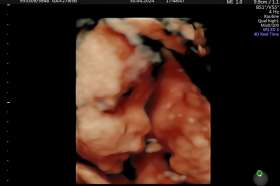

Tomášek - ještě v bříšku

2023-09-26